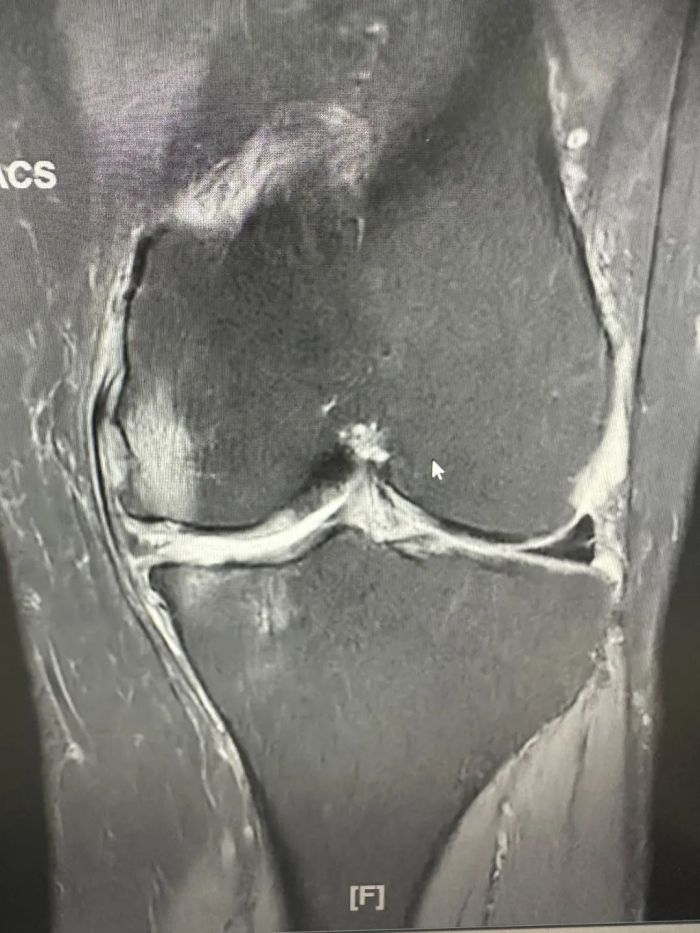

患者蒋先生由于职业原因,长期忍受膝关节疼痛的痛苦,严重影响了日常生活质量。经过中南大学湘雅二医院保膝团队专家吴韧教授及中南大学湘雅二医院桂林医院骨科一病区(关节、脊柱)团队的详细诊断和评估,认为单髁置换手术是目前最适合该患者的治疗方案。

患者术前膝关节情况